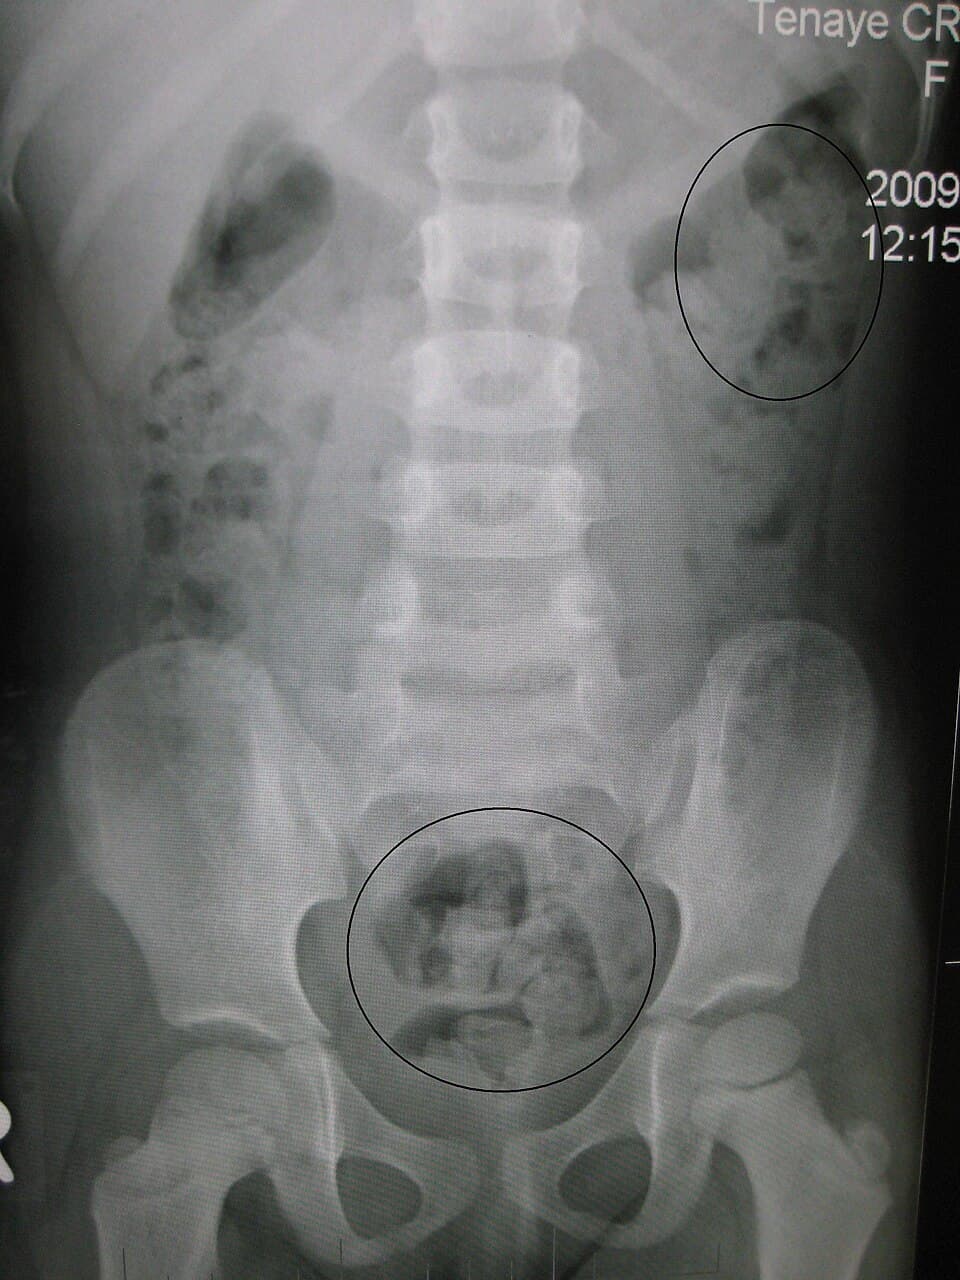

Constipation is a bowel dysfunction that makes bowel movements infrequent or hard to pass. The stool is often hard and dry. Other symptoms may include abdominal pain, bloating, and feeling as if one has not completely passed the bowel movement. Complications from constipation may include hemorrhoids, anal fissure or fecal impaction. The normal frequency of bowel movements in adults is between three per day and three per week. Babies often have three to four bowel movements per day while young children typically have two to three per day. Constipation has many causes. Common causes include slow movement of stool within the colon, irritable bowel syndrome, and pelvic floor disorders. Underlying associated diseases include hypothyroidism, diabetes, Parkinson's disease, celiac disease, non-celiac gluten sensitivity, vitamin B12 deficiency, colon cancer, diverticulitis, and inflammatory bowel disease. Medications associated with constipation include opioids, certain antacids, calcium channel blockers, and anticholinergics. Of those taking opioids about 90% develop constipation. Constipation is more concerning when there is weight loss or anemia, blood is present in the stool, there is a history of inflammatory bowel disease or colon cancer in a person's family, or it is of new onset in someone who is older. Treatment of constipation depends on the underlying cause and the duration that it has been present. Measures that may help include drinking enough fluids, eating more fiber, consumption of honey and exercise. If this is not effective, laxatives of the bulk-forming agent, osmotic agent, stool softener, or lubricant type may be recommended. Stimulant laxatives are generally reserved for when other types are not effective. Other treatments may include biofeedback or in rare cases surgery. In the general population rates of constipation are 2–30 percent. Among elderly people living in a care home the rate of constipation is 50–75 percent. People spend, in the United States, more than on medications for constipation a year.